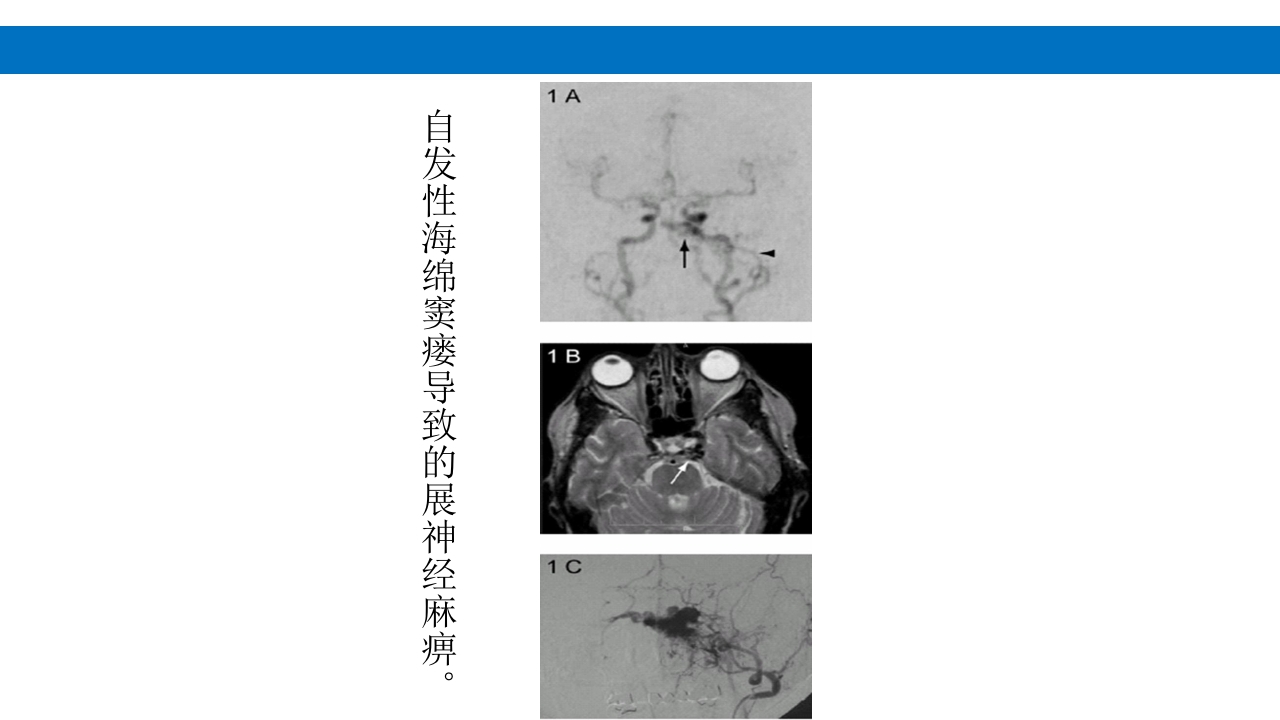

颅脑损伤的并发症及后遗症 讲解人:xxx 20XX年x月x日 1.颅骨骨髓炎 病因:为头皮软组织、中耳、乳突和副鼻窦等处炎性感染而经导 血管侵入颅骨内或颅脑开放伤感染所引起,亦可由菌血症后发生 的细菌栓子由血运转移至颅骨内。 影像学表现: 头部CT: 1.表现为不规则的蜂窝状骨质破坏区,主要位于板障,亦可累 及内外板。 2.破坏区内可见高密度的米粒状细小的高密度死骨。 3.周边可见骨质硬化增生,颅板外无骨膜反应。 4.局部的头皮可见软组织肿胀。 头部MRI: 由于受累部位细胞成分和水量增多,T1WI为低信号, T2WI为高信号,急性期边界不清,慢性期病灶局限, 边界清晰。MRI显示骨质破坏没有CT效果好。 治疗: 除应用抗菌药物控制感染外,当感染局限或已有死骨形成后, 应行手术切除感染...